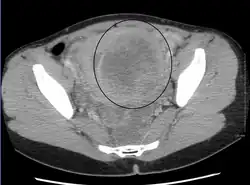

-

A very large (9 cm) fibroid of the uterus which is causing pelvic congestion syndrome as seen on CT -

A subserosal uterine fibroid with a diameter of 5 centimeters -